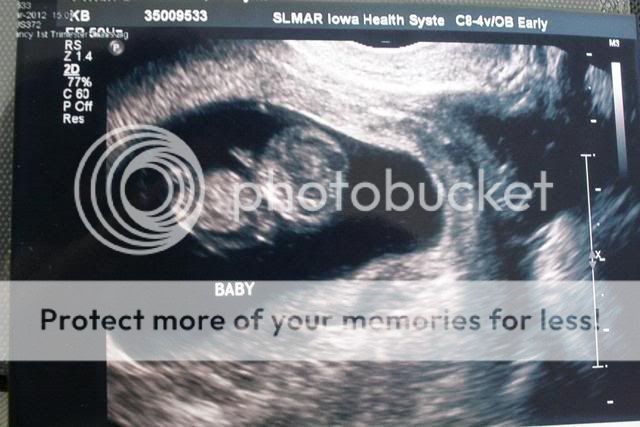

Some of you may have seen my post earlier. I had an ultrasound a few days ago and my doctor called this morning saying he wants to do another one in a week to answer some 'questions' he has. I'm worried. Does my ultrasound look normal or is their something my doctor could be worrying about:

I don't see anything out of the ordinary. If there were some kind of problem, that doesn't mean that it would even show up on that ultrasound. There's a lot of area to cover and look around in there.

Looks perfectly fine to me from just that picture, but I'm not a doctor.